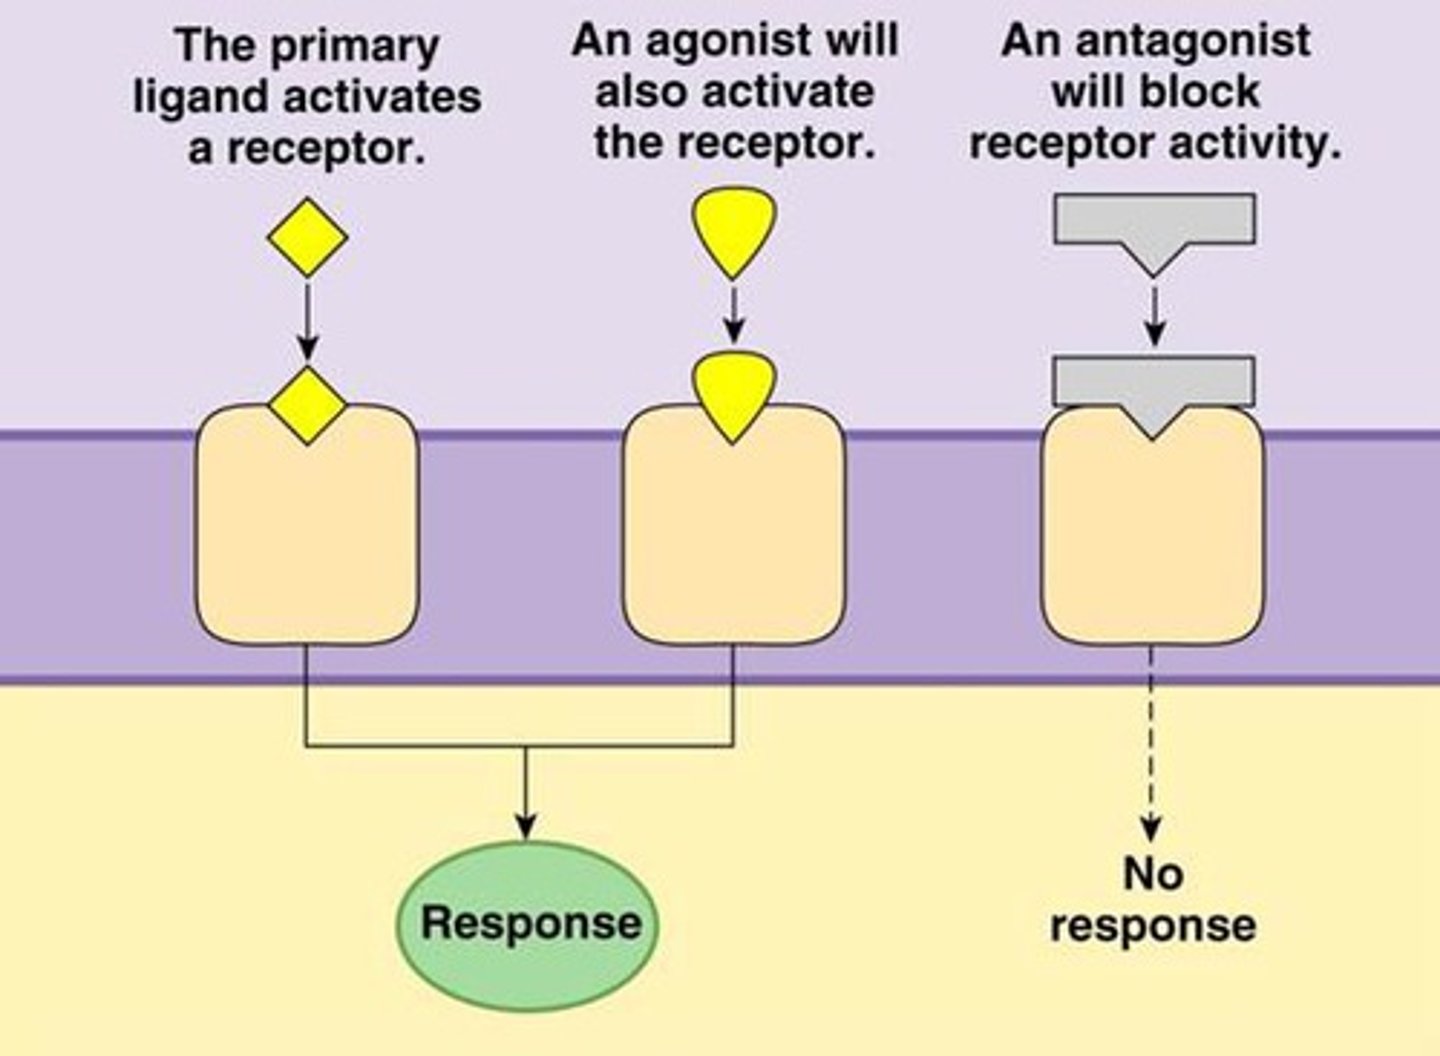

Antagonists

bind to receptors and block a neurotransmitter's functioning

Agonists

these mimic a neurotransmitter and stimulate an action (e.g., morphine mimics endorphins)